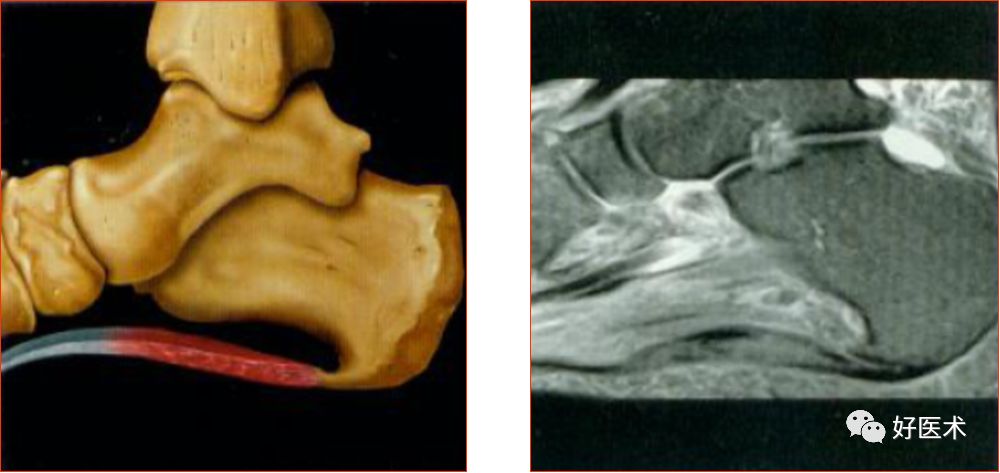

三角韧带

踝关节内侧韧带又称三角韧带,为强劲的三角形纤维束。上方附着于内踝尖及其前后缘;浅层纤维为胫舟部,前行附着于舟骨粗隆,部分与跟舟足底韧带的内侧面融合;中间部为胫跟部,下方附着于载距突;后部为胫距后部,纤维附着于至距骨内侧面和内侧结节。

三角韧带撕裂